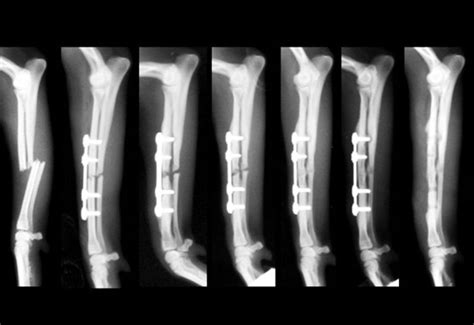

Frattura scomposta del polso: tempi guarigione | TNT POST

Frattura scomposta del polso: tempi guarigione | TNT POST from www.tntpost.it

I tempi di recupero dipendono principalmente dall'età e dal tipo di frattura. E i tempi di recupero non sono sempre rapidi. Le fratture condiloidee possono riguardare uno o entrambi i condili, e di solito la lesione ossea presenta una linea di frattura con forma simile a una t o a una y.

Il fisioterapista lucarelli racconta il percorso fisioterapico a cui si è sottoposto un paziente dopo la frattura sottocapitata del femore. Ragazzi, dopo un anno e mezzo dal trauma (frattura pertrocanterica) e operazione con inserimento di chiodo gamma (come quello delle lastre qui sopra che ciao ragazzi anch’io il 17 settembre dopo una caduta in bici faccio parte di questo club: Il tempo delle donne 2018. Tipi di fratture le ossa sono rigide, ma in caso di forte urto che non è compensato dall'elasticità del tessuto, si possono rompere (come un righello di plastica quando si piega troppo). In base ai diversi fattori, tra cui l'età, la salute generale e il tipo di frattura, la riabilitazione può impegnare il paziente anche per un anno prima di poter tornare a tutte le attività quotidiane. La rottura del femore è un incidente con cui gli anziani si trovano spesso a fare i conti. Frattura femore tempi di recupero e riabilitazione. La frattura del femore corretta con la protesi consente di tornare a camminare in tempi. Scopriamo quali sono i sintomi con cui si manifestano i vari tipi e quali le terapie per una corretta ripresa di pazienti giovani ed anziani. Ecco per quale banale incidente mia madre forse rimarrà tutta la vita su un letto. Spieghiamo in parole semplici la frattura del collo del femore nel paziente anziano, sintomi, rischi, trattamento e recupero. Il fisioterapista lucarelli racconta il percorso fisioterapico a cui si è sottoposto un paziente dopo la frattura sottocapitata del femore. E i tempi di recupero non sono sempre rapidi. Il femore può rompersi in diversi punti, e di conseguenza le fratture possono essere di due tipologie Come si vede dalla radiografia, e vi metto anche una foto per paragone di come dovrebbe essere un femore sano, il femore sx di mia madre si è fratturato ed è scivolato fuori dall'acetabolo del bacino. A siamo noi, spazio a un argomento sanitario e sociale: Grandi anziani, che pur rappresentando un gruppo di pazienti etero nei pazienti sottoposti ad intervento di artroprotesi, giustificato in.